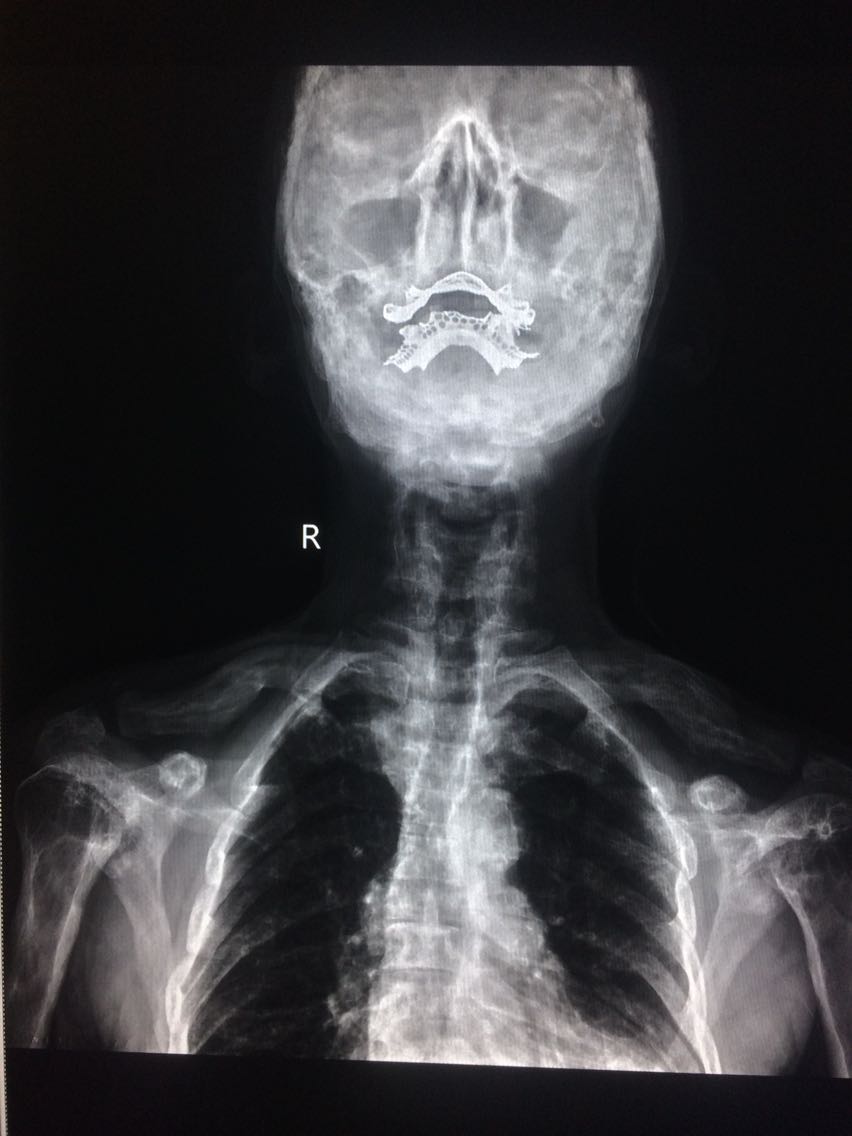

男,65岁 颈部外伤2天。 2天前,在家干农活时,不小心颈部受伤,出现颈部疼痛,活动受限,无恶心,头晕等,遂来诊。 既往无明确病史。

门诊拍片

考虑,佩吉特骨病, 对症治疗。

讨论,该病多见于40岁以上老人,儿童发病少见,具有遗传倾向,大多与病毒感染有关。 无明显症状,并发症较多,对应症状多。 碱性磷酸酶可增高。 棉絮征为颅骨特征性的影像征像。 遂访,注意身体其他部位有没有骨质改变。